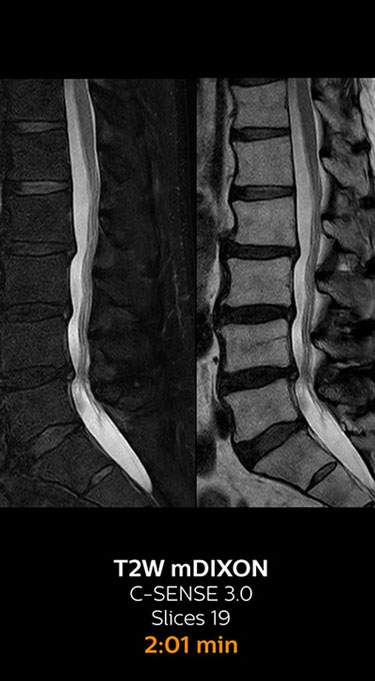

which corresponds to 34% reduction.

With Compressed SENSE, the scan time for the routine lumbar spine examination at KNC was reduced from 11:41 to 8:17 minutes,

MRI examination of the lumbar spine with Compressed SENSE

Ingenia 3.0T CX

Scan time 8:17 min. (was 11:41 min. without Compressed SENSE)